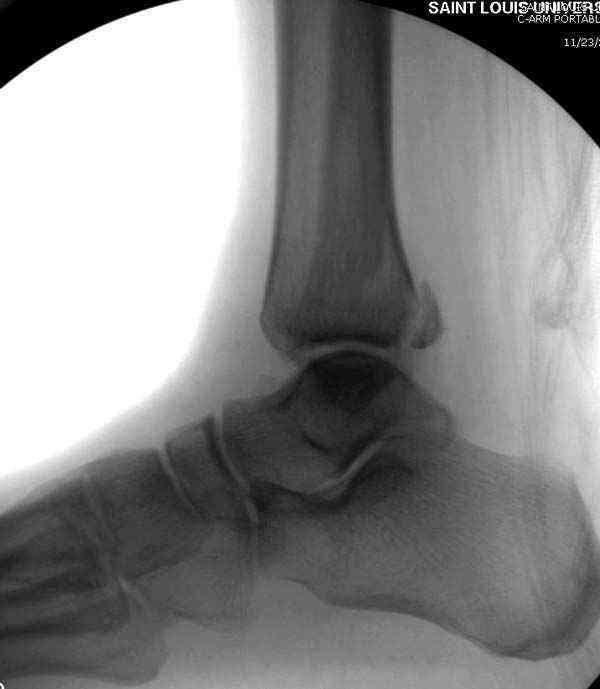

Нет первичных снимков, перелом очень низкий и под большим сомнением диагноз разрыва синдесмоза. Медиальная сторона отрепонирована на "хорошо" и, по-видимому, прорезание проволоки произошло во время операции. Без снимков трудно судить о высоте малоберцовой, а лодыжка находится в варусе. Лагирование получилось, но возле тонких шурупов передне-задний шуруп выглядит немного тяжеловато.

Коллеги правы, что при рутинных переломах достаточным бывает обычные снимки с мортизом. А стрессовые рентгенограммы могут уточнить, есть ли разрыв синдесмоза.

В лечении синдесмоза шурурпы легче установить, и, тем более, они намного дешевле, чем болт-стяжка. От болтов еще и часты осложнения - медиальные пролежни.

При лечении синдесмоза количество шурупов не имеет значения. Два через три кортекса или один через все кортикальные слои механически одинаковы.

Здесь несколько частных случаев: перелом голеностопа со сравнительными снимками и разрыв синдесмоза, а также медиальная Hook пластина.